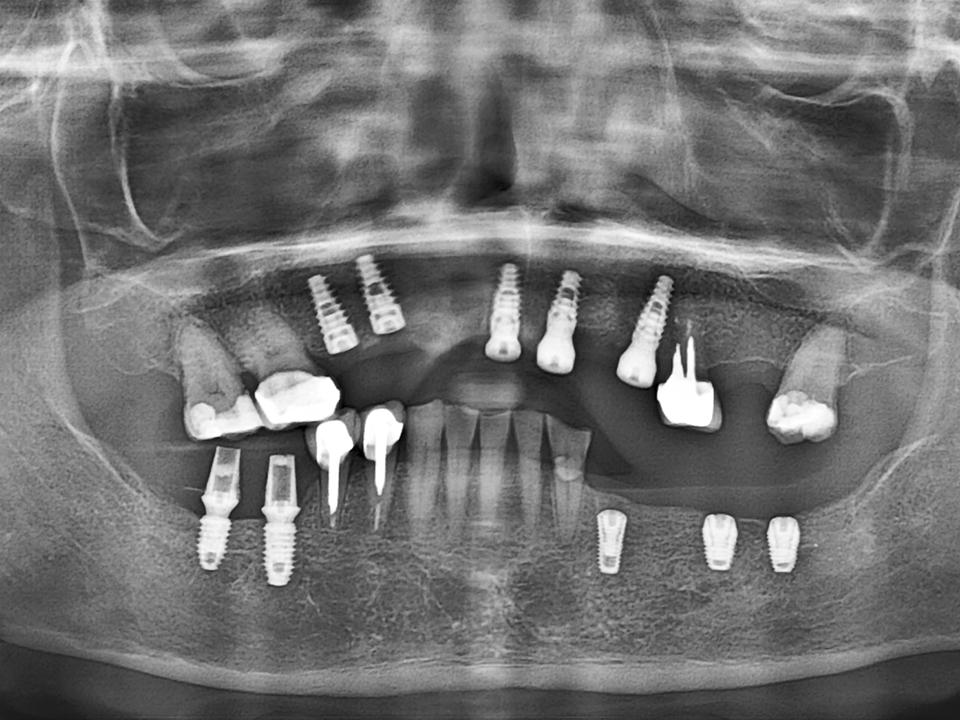

ALL ON全口重建

術式介紹

ALL ON全口重建是由4-6 顆植體(依條件而定)成,專為多顆缺牙或全口無牙患者設計的創新全口重建技術,僅需4-6 支植體即可支撐一整排固定式假牙,大幅減少手術次數與成本,並縮短療程時間。